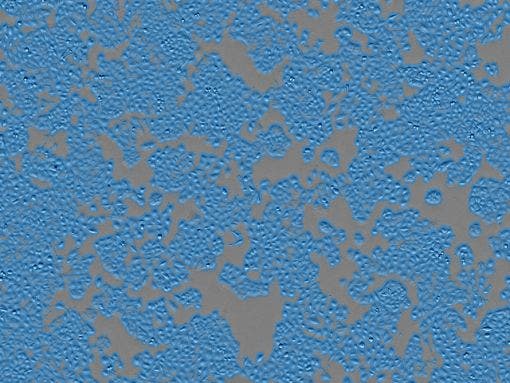

Células de cáncer de mama (MCF7)

Condiciones del recipiente: Placa de 96 pocillos. Tiempo de intervalo: 1 hr. Período de medición: 7 días.

Recuento de células : 1.85 × 10³

Confluencia : 53.81%

Resultados analíticos